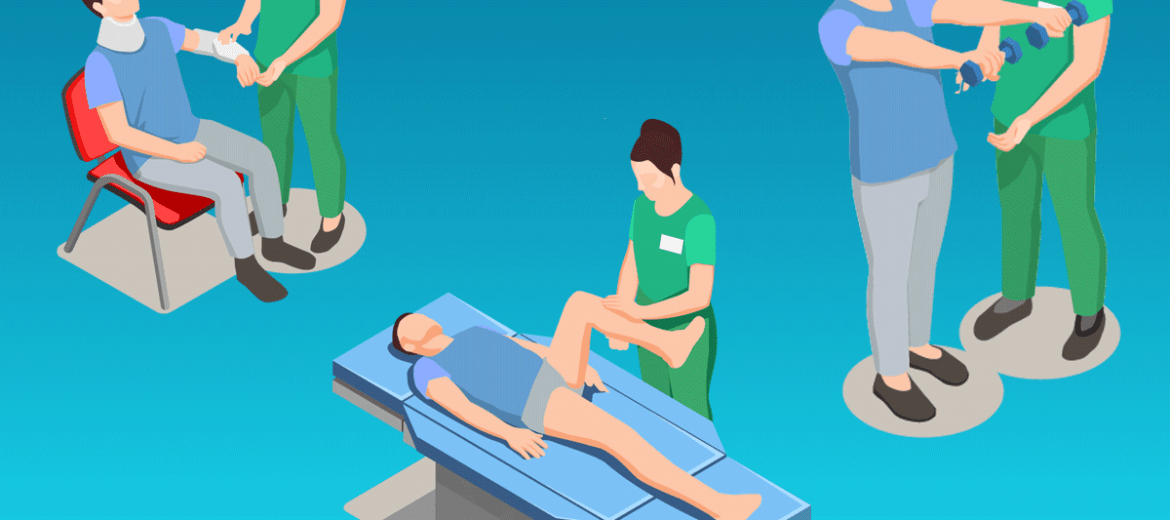

Para a fisioterapia o foco será alinhar a drenagem linfática à técnicas de terapia manual para liberação das tensões teciduais em região da coluna e pelve e assim garantir a manutenção do quadro de dor e desconforto tão críticos no terceiro trimestre.

Nas técnicas de liberação de tensões a pompagem e a distração de fáscia tóraco lombar, são as mais indicadas . Já para coluna torácica a reeducação e conscientização postural , mobilidade ântero-posterior de tórax, associado a respiração diafragmática são excelentes aliadas no alívio das tensões. Por fim a coluna cervical ombros , pescoço e cabeça podem ser trabalhos com técnicas de quick massagem em cadeira com adaptação em região abdominal.